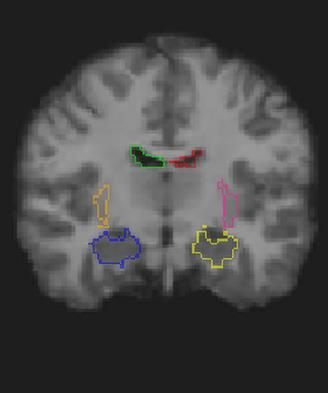

Medical image registration is a fundamental and critical task in medical image analysis. With the rapid development of deep learning, convolutional neural networks (CNN) have dominated the medical image registration field. Due to the disadvantage of the local receptive field of CNN, some recent registration methods have focused on using transformers for non-local registration. However, the standard Transformer has a vast number of parameters and high computational complexity, which causes Transformer can only be applied at the bottom of the registration models. As a result, only coarse information is available at the lowest resolution, limiting the contribution of Transformer in their models. To address these challenges, we propose a convolution-based efficient multi-head self-attention (CEMSA) block, which reduces the parameters of the traditional Transformer and captures local spatial context information for reducing semantic ambiguity in the attention mechanism. Based on the proposed CEMSA, we present a novel Symmetric Transformer-based model (SymTrans). SymTrans employs the Transformer blocks in the encoder and the decoder respectively to model the long-range spatial cross-image relevance. We apply SymTrans to the displacement field and diffeomorphic registration. Experimental results show that our proposed method achieves state-of-the-art performance in image registration. Our code is publicly available at \url{https://github.com/MingR-Ma/SymTrans}.